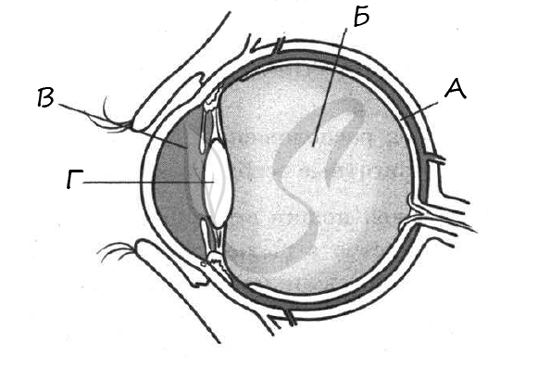

КТ-графики и изображение строения глаза